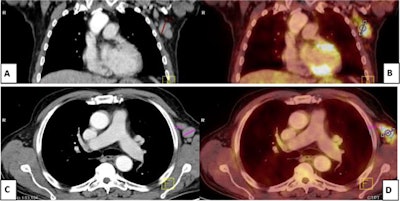

Previous research has shown that enlarged and sometimes painful swollen lymph nodes can occur in cancer patients within days following COVID-19 vaccinations. These cases of vaccine-associated hypermetabolic lymphadenopathy (VAHL) can confound PET/CT findings related to a patient's malignant lymphadenopathy, primarily due to the ability of F-18 FDG-PET/CT scans in detecting "hot" nodes, even if they are normal.

According to the findings, hypermetabolic lymph nodes were identified ipsilateral to the vaccine injection site in 66 of 120 vaccinated patients (55%). The authors noted that the incidence and grades of VAHL were higher within the first week following the second vaccine dose than the second and third weeks and that patients younger than 60 years old showed higher incidence and grades of VAHL than those older than 60.